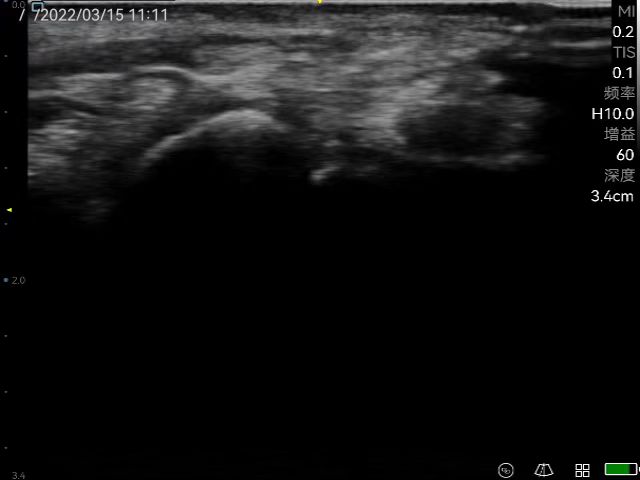

Precisely guided drug injection around the knee joint.

Visualized diagnosis and treatment injection technology for related painful diseases such as head and face, limbs, trunk, joints, musculoskeletal, chest and abdominal wall, and nerve block in corresponding parts.